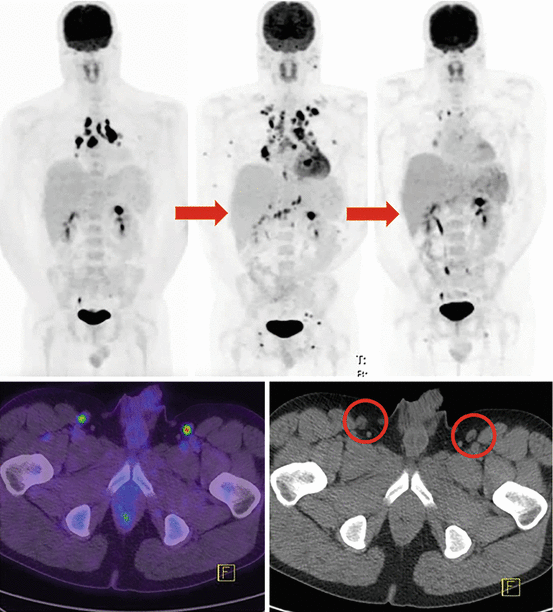

PETCT scan revealing metastatic melanoma in groin image Pet Ct Scan For Melanoma A pet scan can help show if the cancer has spread to lymph nodes or other parts of the body. Positron emission tomography (pet) scan. Pet Ct Scan For Melanoma.